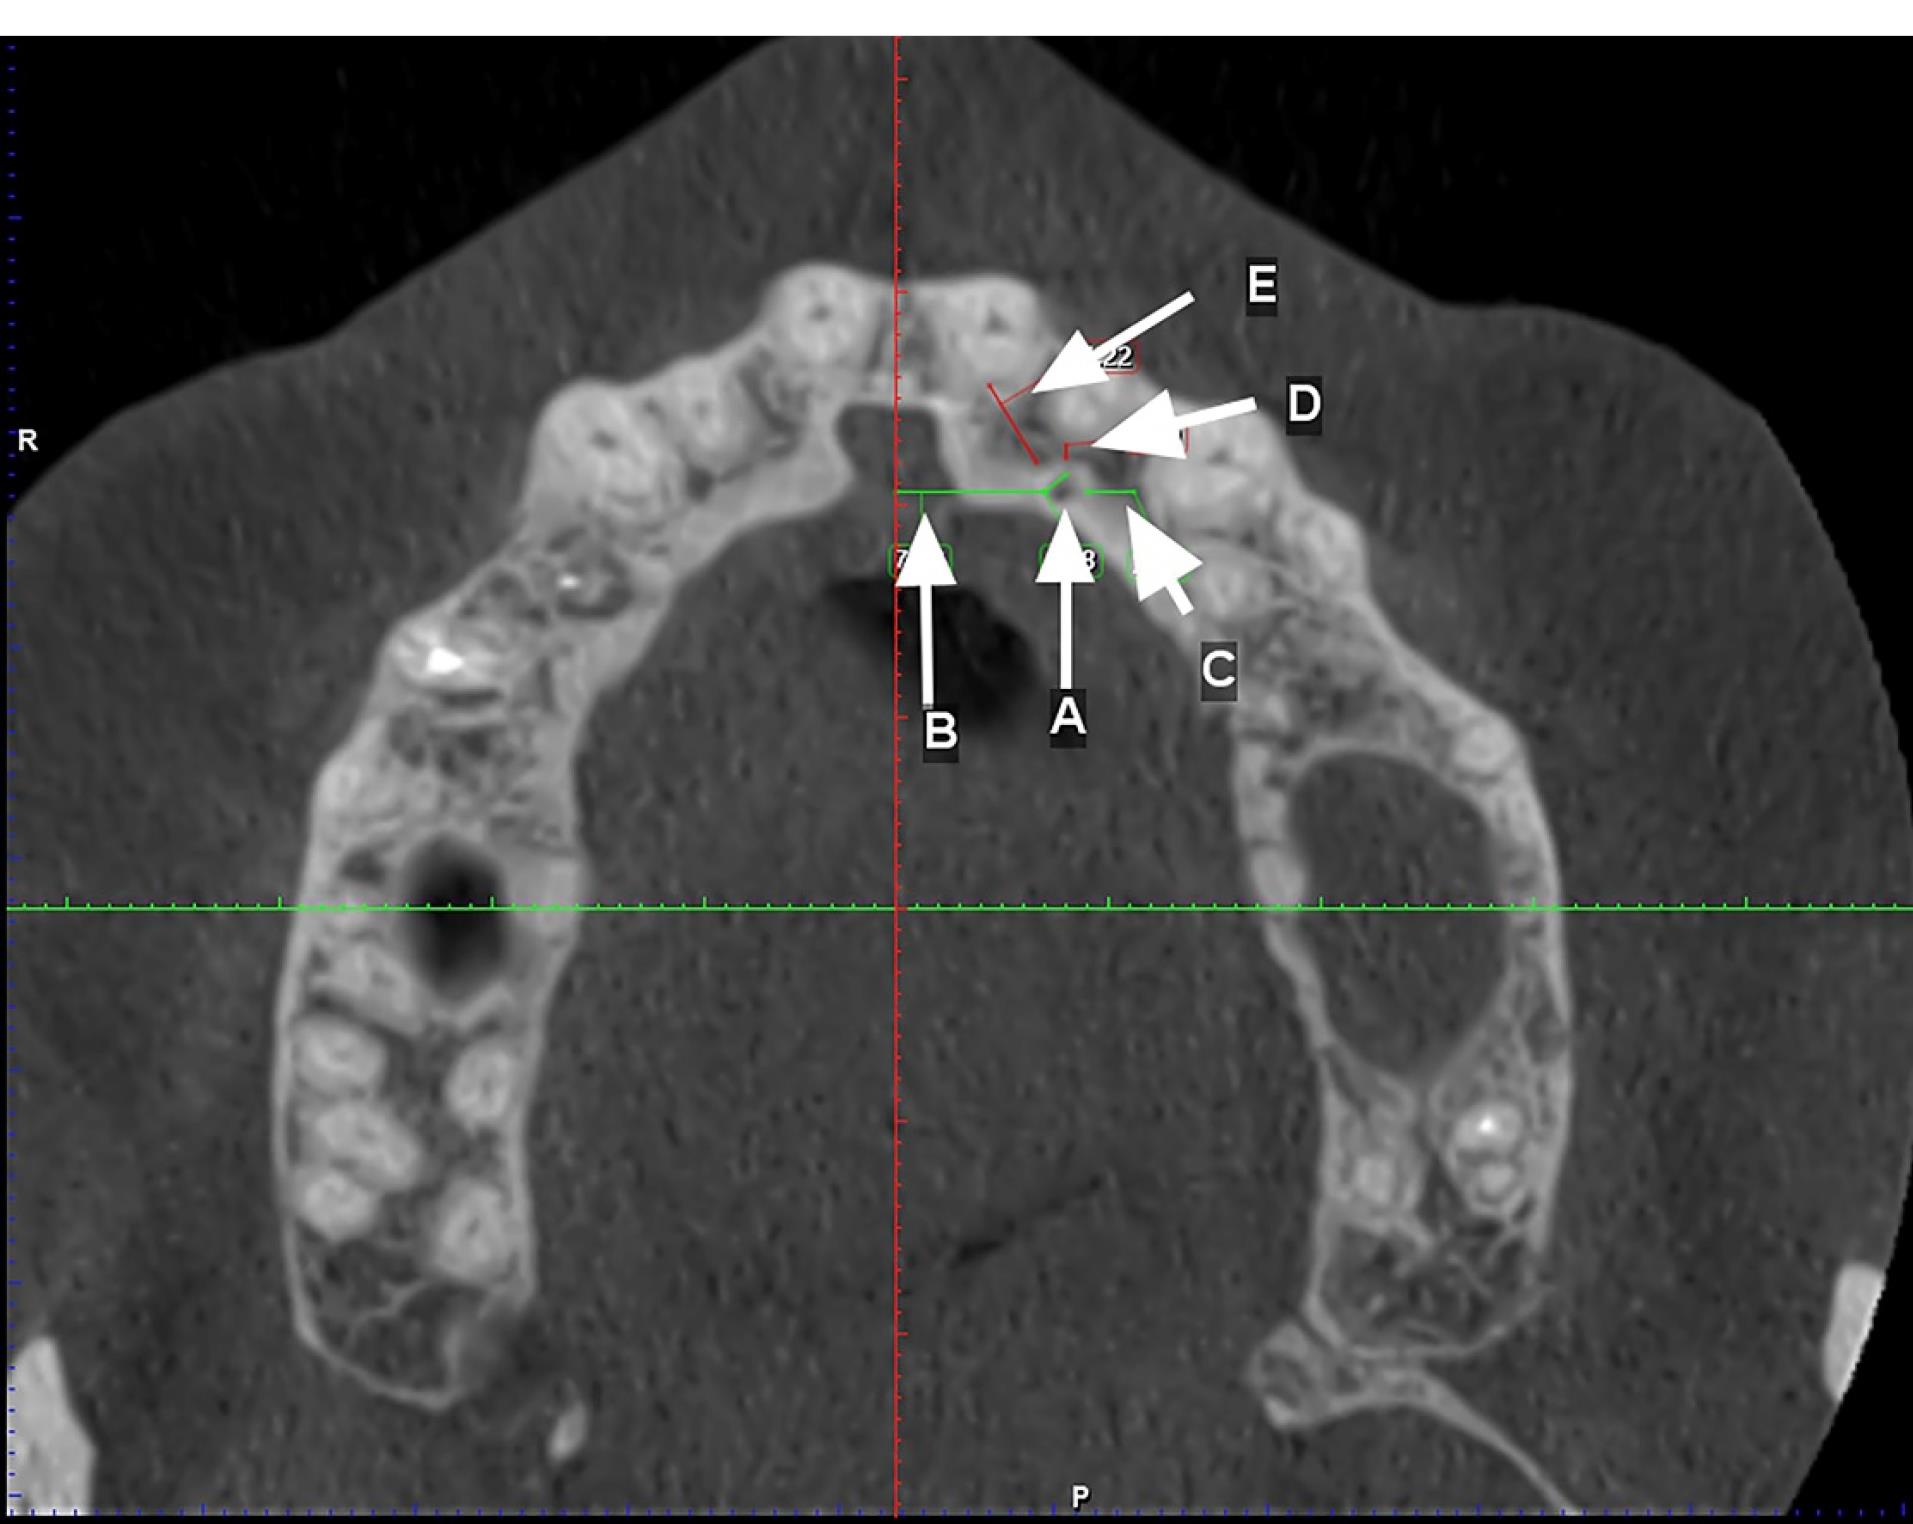

Two observers investigated all the images twice with a time interval of one month. The first observer was an experienced periodontist, and the second observer was an experienced oral and maxillofacial radiologist. Observations and measurements were carried out by Planmeca Romexis software version 3.8.1. The presence of CS was defined in axial and sagittal planes, and its clear extension was confirmed in the coronal sections. CS diameter was measured on the axial plane. Canals with a diameter of > 1 mm and a definite extension to the infraorbital canal were considered (Figure 1). Slice thickness and interval were 0.5 in all the sections. The axial plane in which the CS had the largest diameter was chosen to measure the distance of the CS to the adjacent teeth and the nasopalatine canal. The tooth with the closest distance to the CS was considered the main tooth; then, the mesial, mid, or distal position of the main tooth related to the CS was determined. The distances of CS from the nasal floor, ridge crest, buccal cortical plate, and the distance of canal extension from the main tooth apex were measured on the cross-sections perpendicular to the axial plane at the CS site (Figures 2 and 3).

Figure 1.

Axial and coronal views of the CS